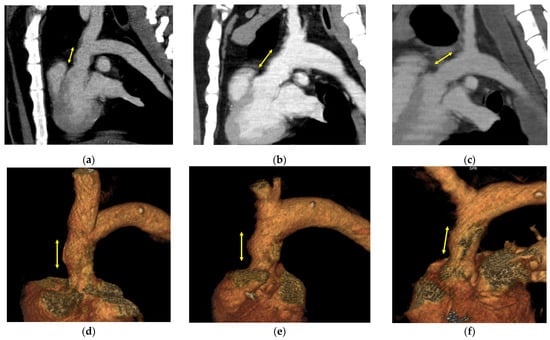

3.2. Image Evaluation